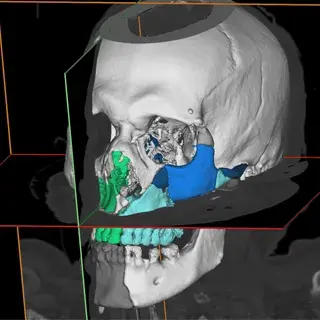

3D Systems' VSP® surgical planning solutions for craniomaxillofacial (CMF) applications received FDA clearance as a service-based approach to personalized surgery over 10 years ago.

3D Systems and Stryker Corporation have partnered to provide surgeons with best-in-class products and services for craniomaxillofacial surgeries. As a leader in personalized healthcare solutions, 3D Systems has planned and delivered devices for more than 140,000 patient-specific cases. The Stryker Craniomaxillofacial business specializes in providing patient-specific options and innovative solutions that help drive efficiencies in surgical suites. The combination of Stryker’s specialized team and advanced implants with 3D Systems' cutting-edge 3D printing technologies and expert consulting services positions both companies to provide a superior level of service to healthcare professionals who use these revolutionary solutions.